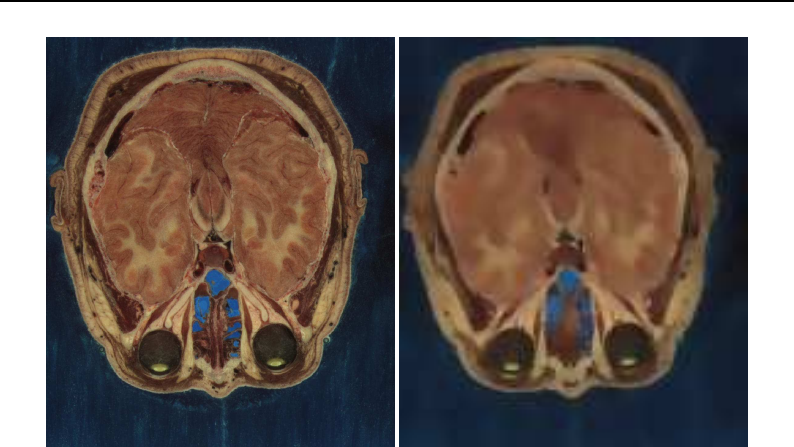

The Insight Toolkit was designed to support the Visible Human Project and its as-

sociated data. This data is available from the National Library of Medicine at

http://www.nlm.nih.gov/research/visible/visible_human.html